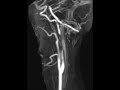

Internal Carotid Artery Dissection

These images demonstrates a 2.5 cm “flow gap” of the right internal carotid artery approximately 3 cm distal to the carotid bifurcation. T1 images show hyperintensity in the vessel wall compatible with hemorrhage resulting in near occlusion of the vessel. Findings represent dissection and this location is the most common site. 20% of ICA dissections are bilateral or involve the vertebral arteries. The etiology of dissection can be grouped into post-traumatic, idiopathic/spontaneous, or those resulting from an underlying arteriopathy such as marfan’s syndrome. Treatment usually entails anticoagulation therapy unless contraindicated by intracranial hemorrhage.